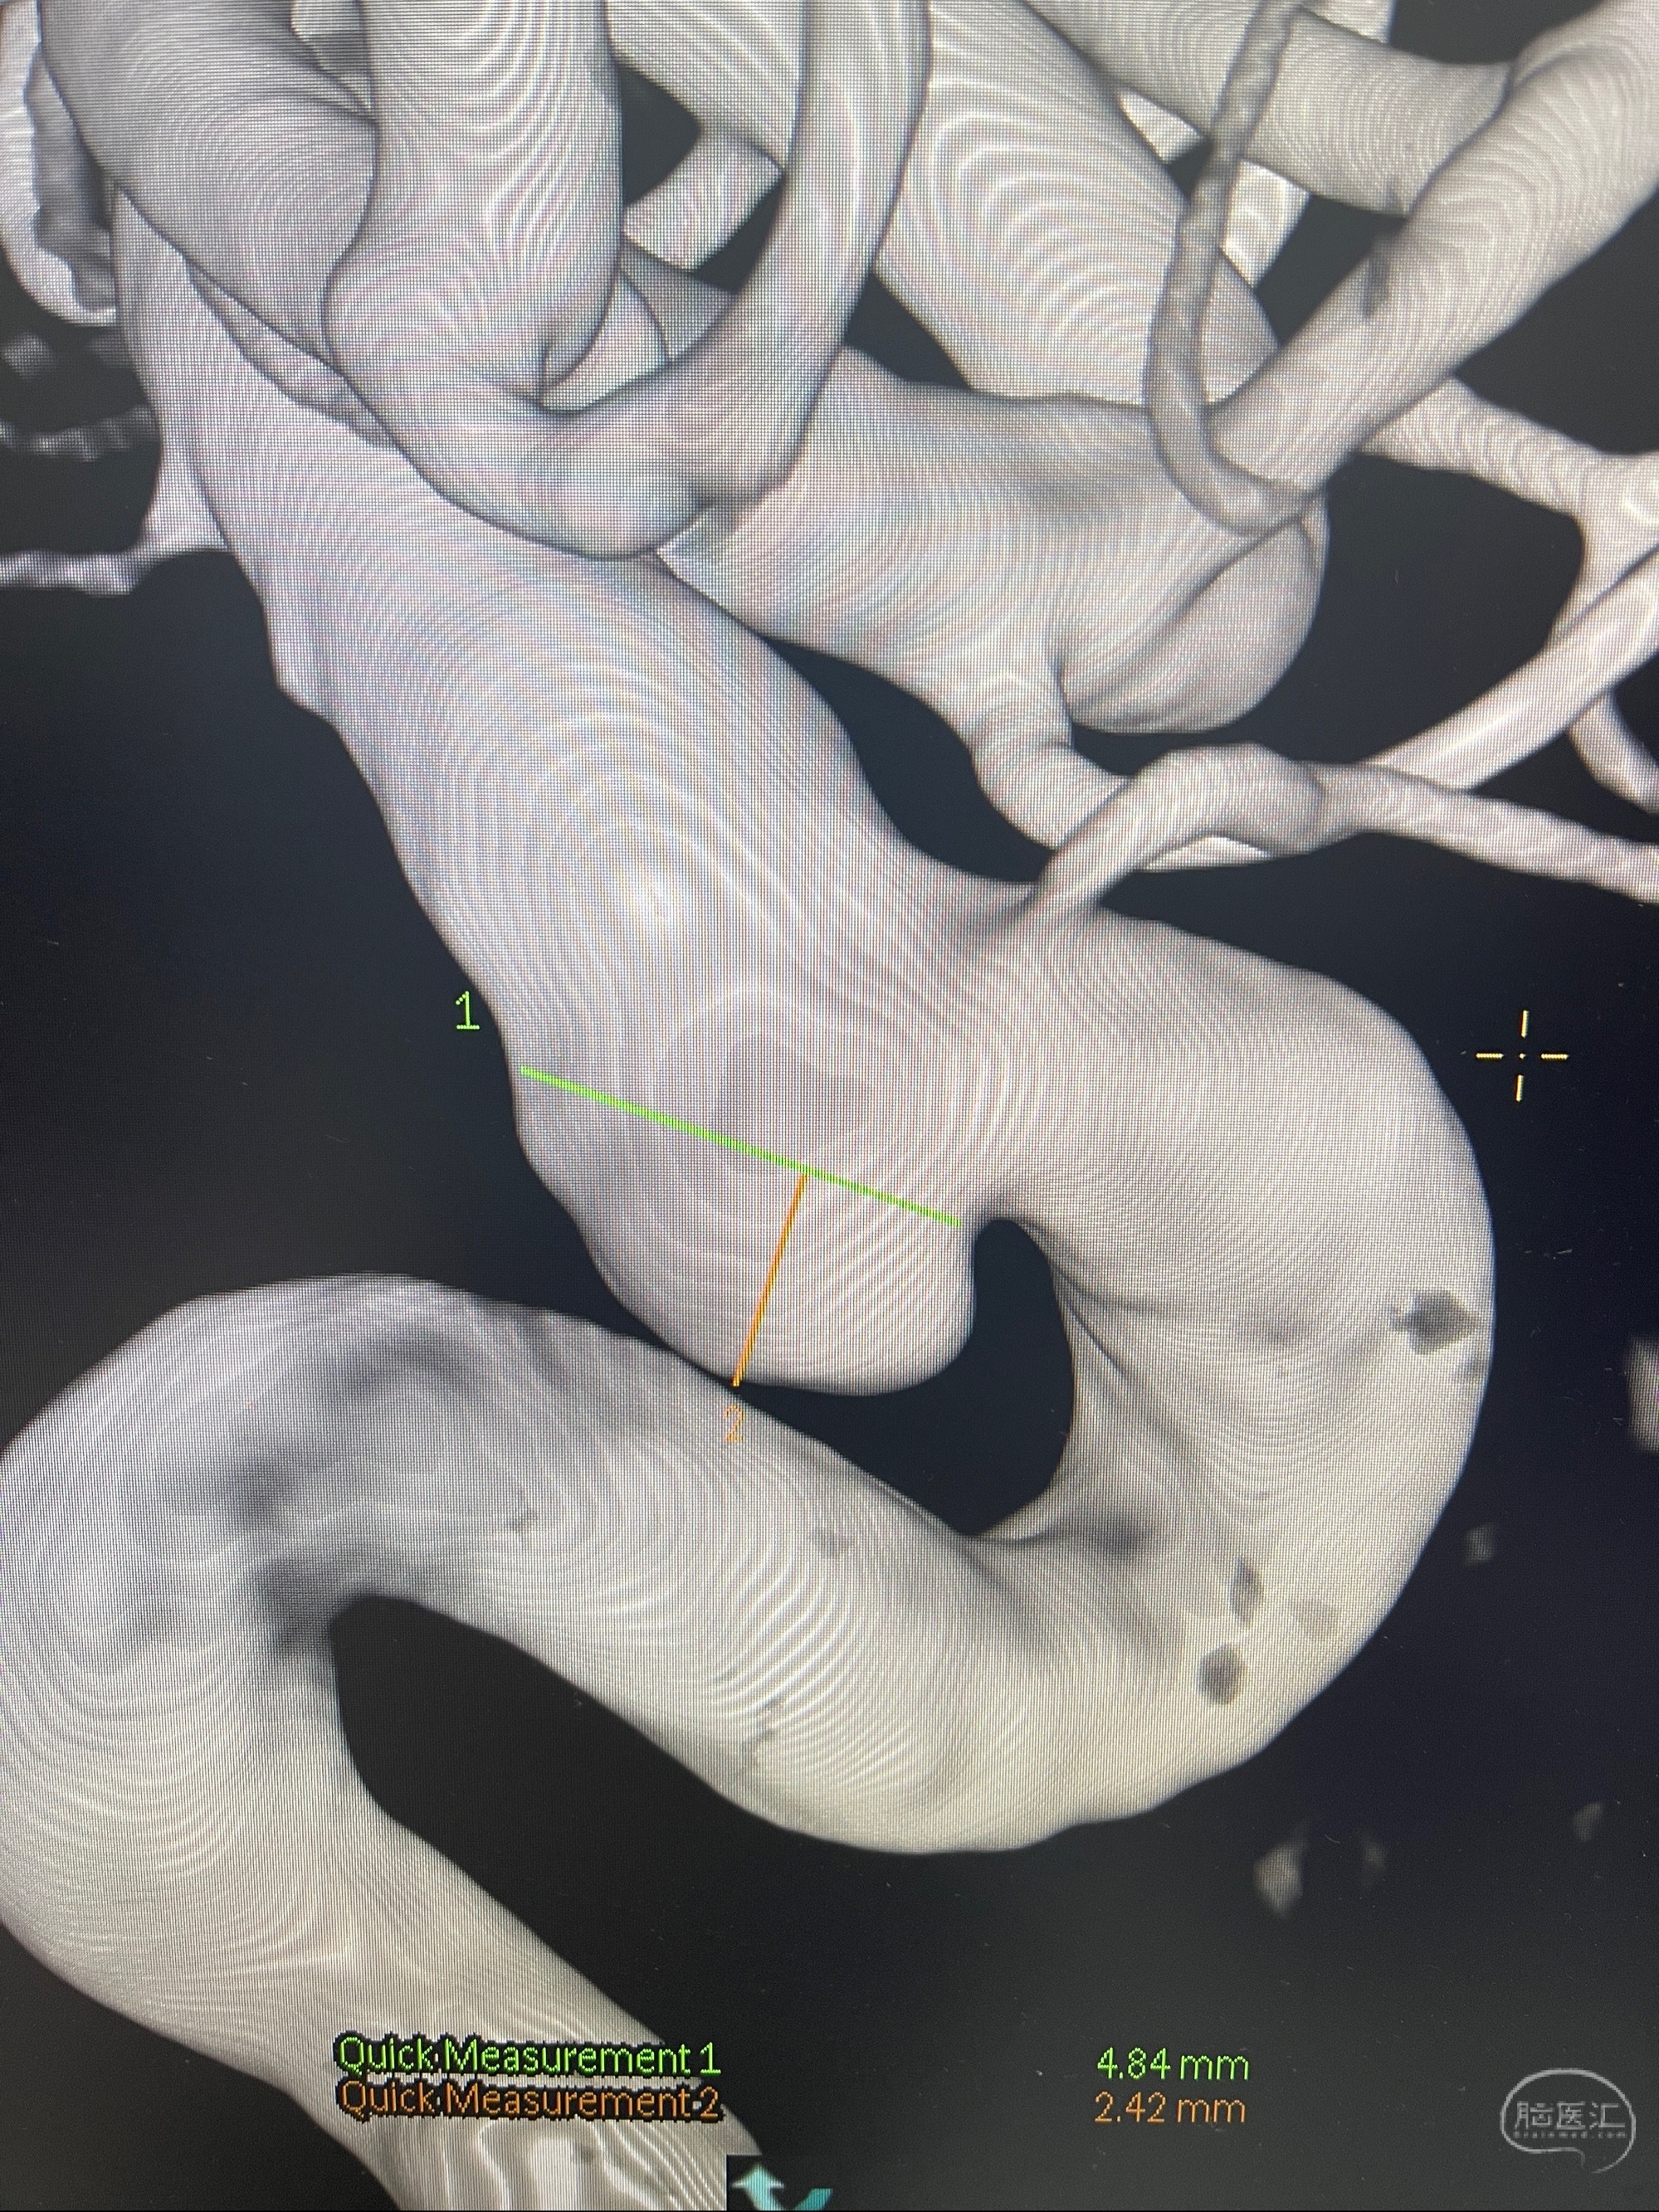

CTA示:右侧颈内动脉C6段见指向下方的突起,余左侧颈内动脉、双侧椎动脉、大脑前动脉、大脑中动脉、大脑后动脉及基底动脉走形正常,未见明显扩张及狭窄,局部未见明显瘤样扩张。

2023-07-27全脑血管造影:双侧颈内动脉眼动脉段动脉瘤,右侧较大

2023-08-01全麻下行双侧颈眼动脉瘤支架辅助栓塞

- pipeling4.5-20mm

- pipeline 4.0-20mm